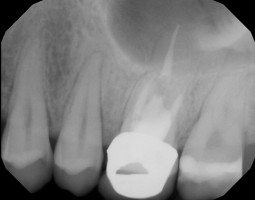

Finding Decay Earlier

The Diagnodent is a laser cavity detector. It uses a low-level laser signal that is beamed into the tooth. It measures the reflection (fluorescence) coming back at it, and creates a digital readout from 0 to 99. Strong healthy teeth will have very low numbers. Decay is indicated by higher numbers and exposed decay will register a 99. The Diagnodent can effectively look through the enamel and determine if there is decay underneath it. It is particularly useful in the pits and fissures on the chewing surface of a tooth. Often times the enamel is strong and hard, yet the bacteria are able to get into the inner part of the tooth through the smallest gap, and start decaying the tooth under the enamel.

This happens even though the tooth looks fine to the naked eye or to the traditional method to detect decay called dental pick or explorer. What often happens without the Diagnodent is decay goes undetected for years, and when it is finally discovered it is a big, expensive problem. The Diagnodent is one of the key tools in Minimally Invasive Dentistry. We use the analogy of the Diagnodent to radar or sonar in assessing the status of the density of the tooth. Early caries detection is coupled with conservative restoration using Air Abrasion in saving the strength of a tooth for a lifetime. Who would like to catch decay early and save the strength of the tooth?

Root canal therapy is necessary when the pulp of a tooth has died from either trauma or infection. Many of our forward thinking technologies such as lasers, ozone and air abrasion tend to help the pulp of a sick tooth recover and heal avoiding the need for a root canal. When necessary, we perform root canal therapy using the latest technology. We have advanced technology to locate the apex of the root as well as the most modern techniques for thoroughly cleaning and shaping the inside of the canals of the tooth. Most importantly we use lasers and Ozone inside of the canals, which are the most effective ways of killing bacteria; this leads to a higher success rate. Molar root canals which have multiple canals and are more difficult and lengthy to complete, as well as retreatment of an old or failing root canal are often times referred to the endodontist or root canal specialist.